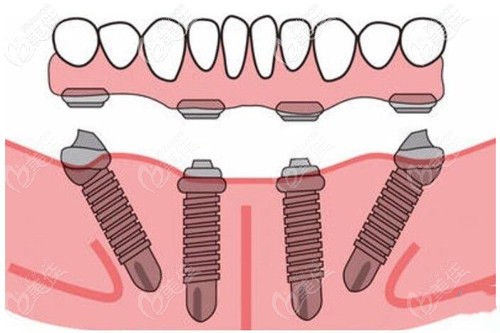

比较合适的方案就是做拔掉残余的牙齿,上牙种植6颗、下牙种植6的全口即刻种植、即刻修复。可以避免植骨粉,还能当天种牙后,就能戴牙冠,回家就能正常吃饭啊什么的。

因为也知道姥爷的牙齿情况,所以我就替他决定了做这个allon-6全口种植,选择的是进口的登腾种植体,一共十来万吧,相对种植牙的价格来讲,性价比高些。